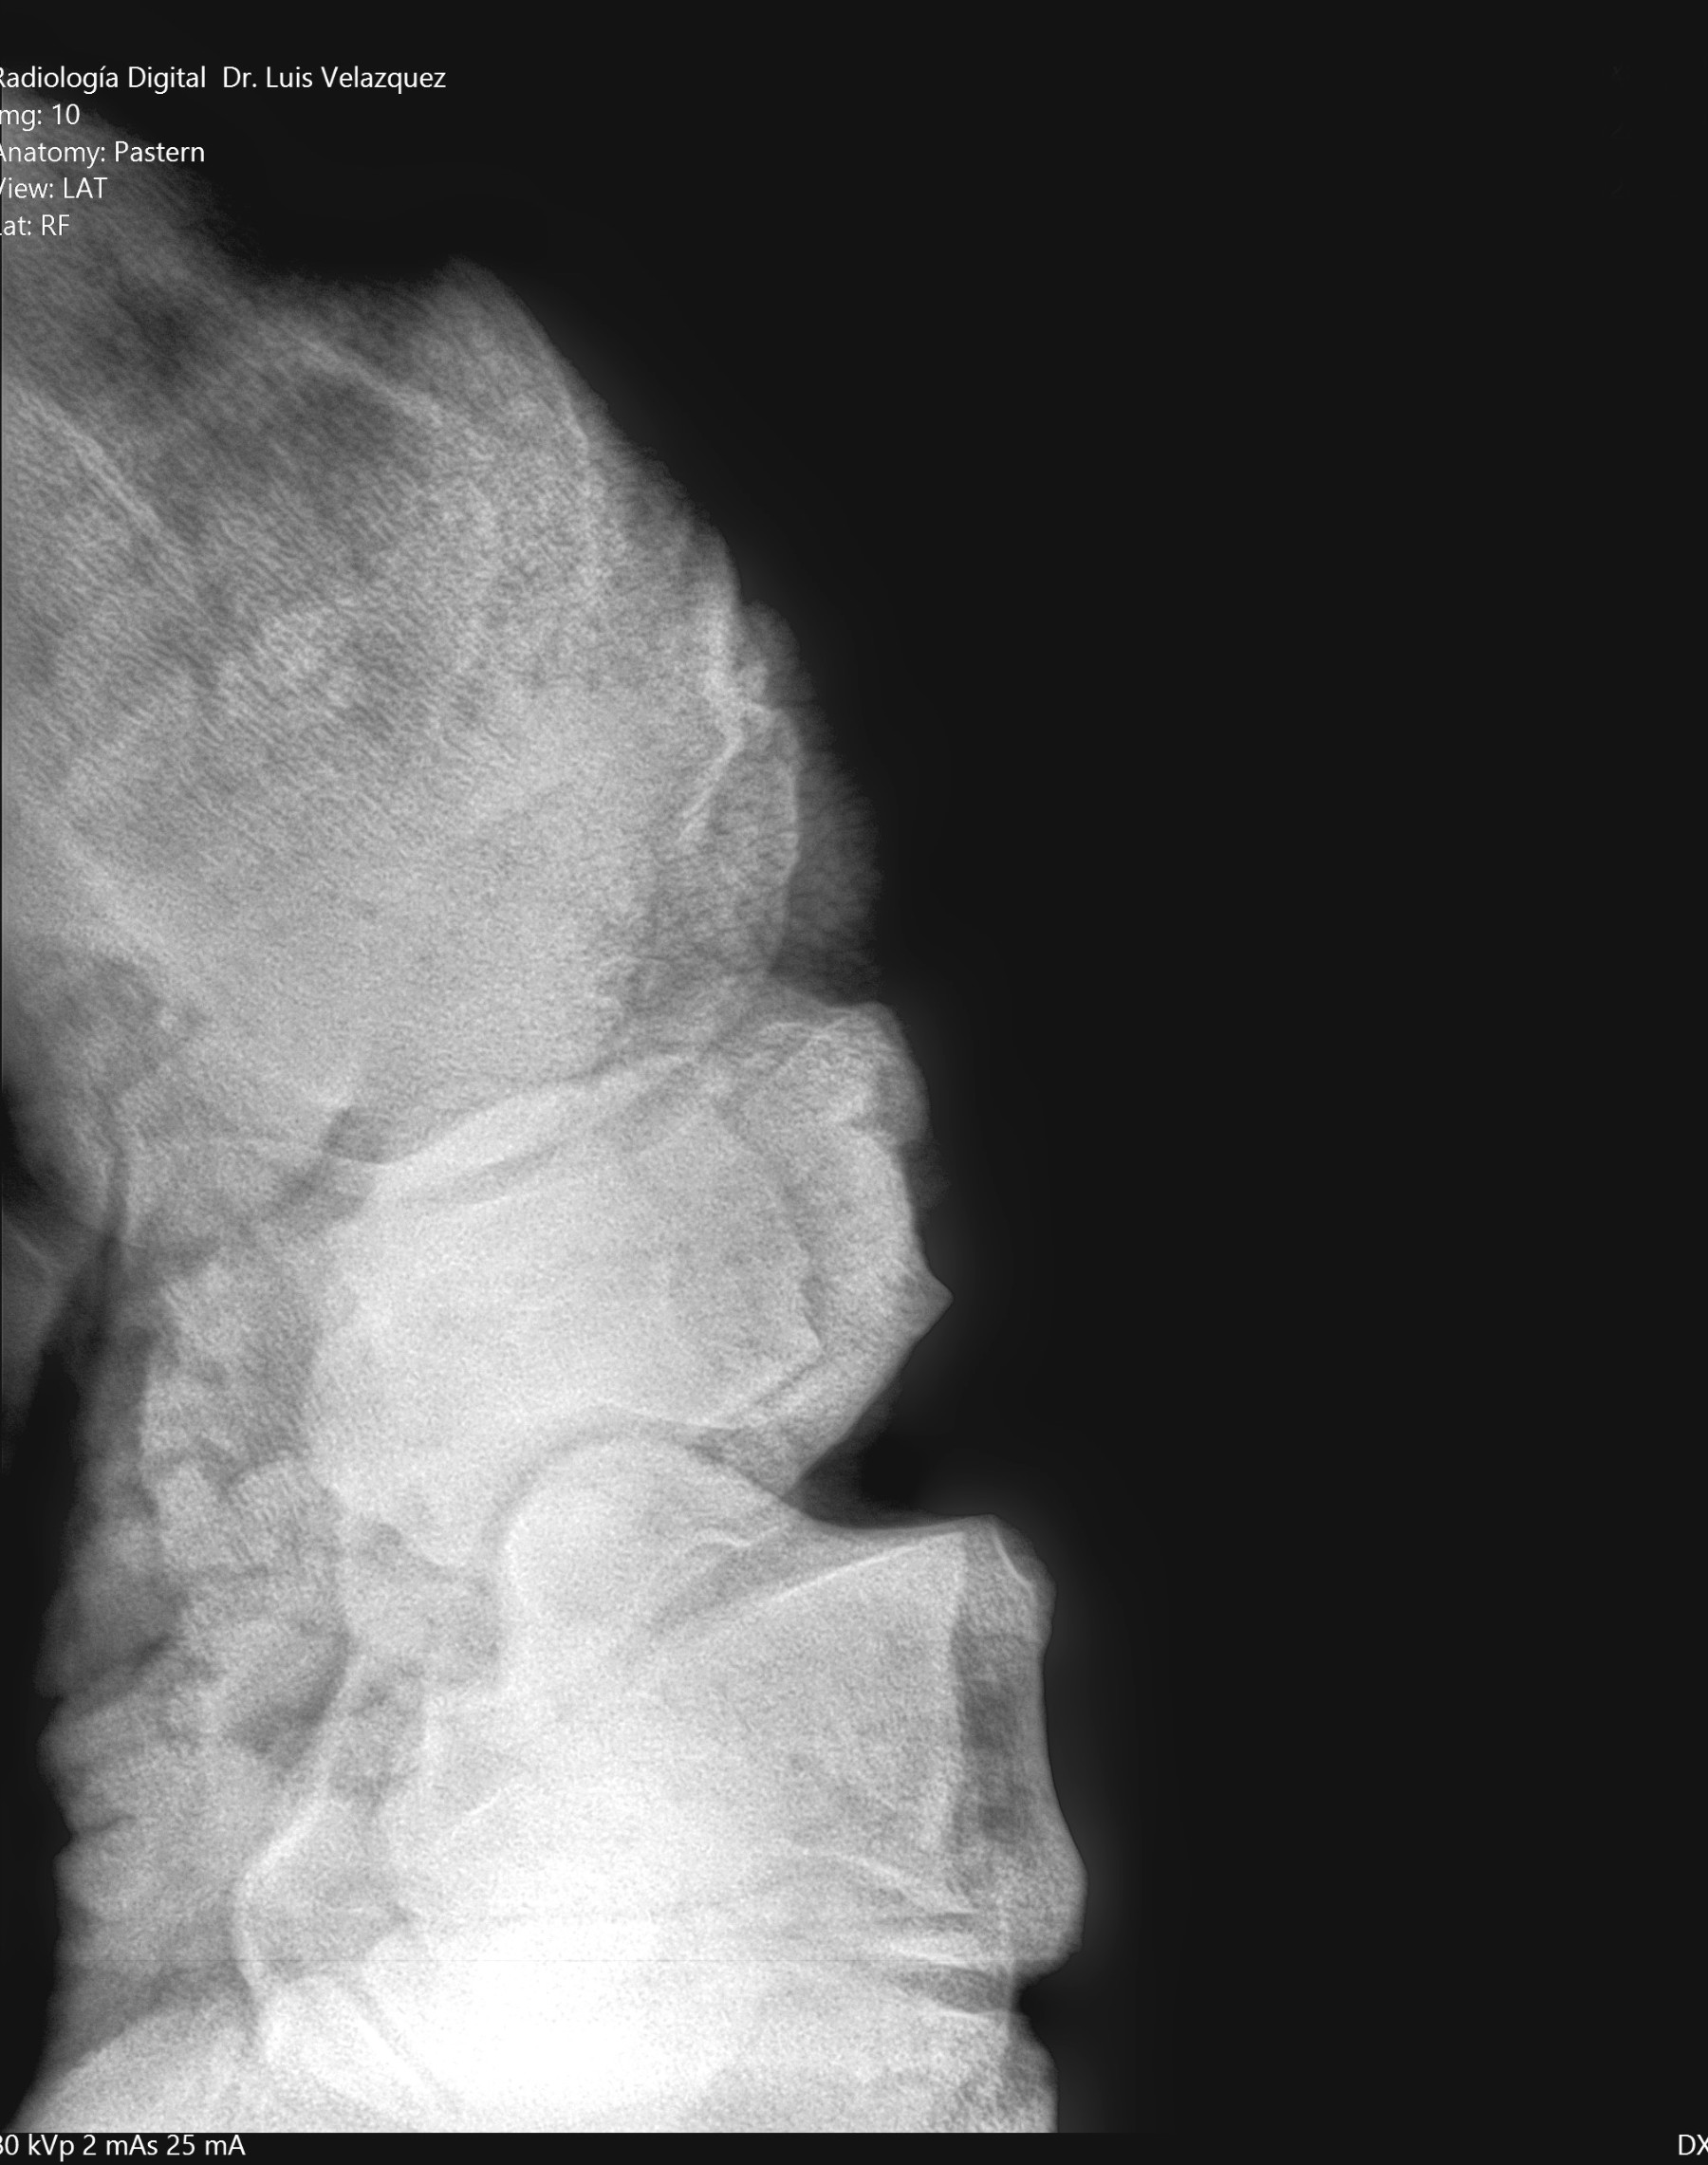

Cambios Térmicos en las Extremidades de Caballos,

Asociados a Golpes y su Evaluación por Termografía.

Los caballos de salto, en competencia, pueden derribar obstáculos y lastimarse. Si se golpean, no siempre claudican. Considerando al calor como un signo de inflamación, se evaluaron los cambios térmicos de 6 áreas de las extremidades torácicas y pelvianas de 23 caballos de salto en nivel de competencia de 1.05 a 1.60 m de altura, por medio de termografía durante 4 días de competencia (N=2208 áreas).